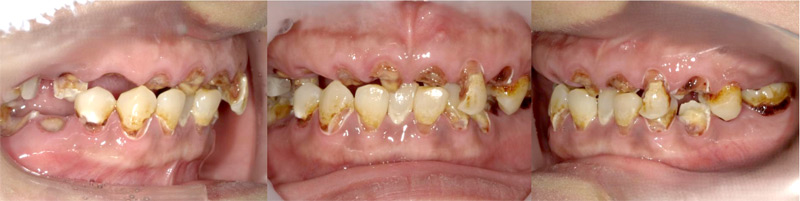

上顎、下顎のいずれか1列分の歯を、4本のインプラント体で固定する治療についての症例です。

施行名 : 審美歯科(虫歯などをインプラント体によって改善する施術)

副作用やリスク : 麻酔で腫れやむくみを生じる場合があります。

また、劣化や口内の手入れを怠ることにより脱落する場合があります。

施術の価格:8万〜90万(税抜き)

※個人差があり、効果を保障するものではありません